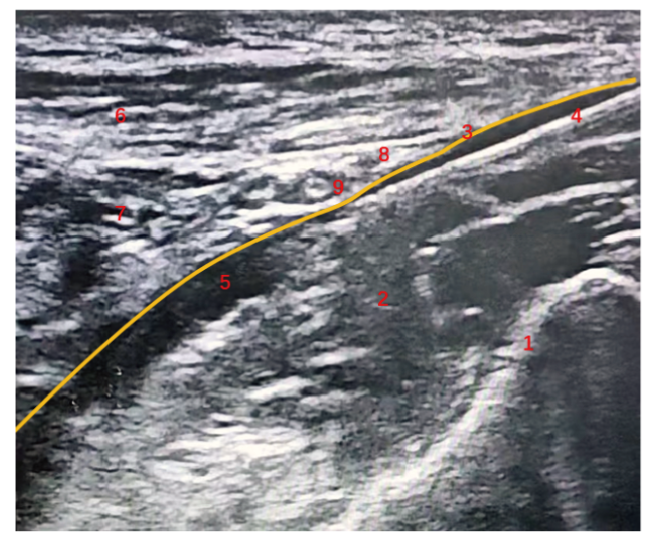

术前常规禁饮禁食,入室后开放上肢静脉通路补液;常规监测患者各项生命体征,如血压、心率(heart rate,HR)、心电图(electrocardiogram,ECG)、脉搏血氧饱和度(pulse oxygen saturation,SpO2)和脑电双频指数(bispectral index,BIS)。B组于麻醉诱导前先行超声引导下腹股沟韧带上髂筋膜阻滞:患者取仰卧位,触诊确定髂前上棘,将高频线阵探头置于髂前上棘内侧,与脐连线外1/3处,调整探头使成像清晰,辨别髂骨、髂腰肌、髂筋膜和旋髂深动脉,见图1。消毒铺巾后,采用平面内进针技术,从髂前上棘处进针,针尖到达髂肌表面后给予2 mL生理盐水进行水分离试验。若液体沿髂腰肌表面呈线性扩散,表明位置正确,给予0.25%罗哌卡因30 mL完成注射。操作完成后间隔5 min测试股神经、股外侧皮神经及闭孔神经皮区感觉,以针刺痛觉减退或消失为阻滞成功。

图 1 超声引导下腹股沟韧带上髂筋膜阻滞示意图

注:1为髂骨,2为髂腰肌,3为髂筋膜,4为神经阻滞针进针处,5为局麻药进针处,6为腹内斜肌,7为腹横肌,8为旋髂深动脉,9为髂腹股沟神经。

Figure 1 Schematic diagram of ultrasound-guided suprainguinal fascia iliac block